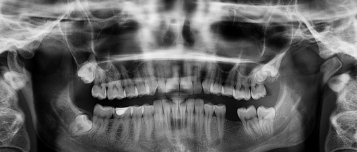

우식치아는 흔히 '충치'로 불리며, 치아 표면이 손상되고 치아 내부가 부패되는 치과 질환입니다. 초기에는 큰 증상이 없지만, 방치하면 통증과 염증을 유발하고 치아를 상실할 위험이 있습니다. 이번 글에서는 우식치아의 뜻과 원인, 증상, 치료 방법에 대해 자세히 알아보겠습니다.

우식치아란 치아가 산(acid)이나 박테리아에 의해 손상되어 부패하는 상태를 의미합니다.

- 치아 표면의 에나멜층(법랑질)이 약해지고, 점차 내부의 상아질과 치수(신경)로 손상이 진행됩니다.

- 주로 치아 위에 남은 음식물과 세균이 결합해 생기는 산이 원인입니다.